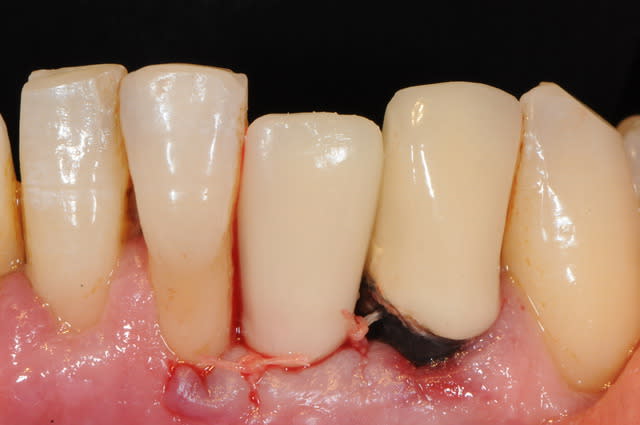

et ici ?? vous feriez quoi ?

32 et 42 pas mobiles

malheureusement, l'espace est réduit pour mettre deux implants.

comment avez vous déjà géré ce type de cas ??

le haut est déjà traité...

Img 0064 fykvs7 - Eugenol

Img 0066 bpmgnj - Eugenol

R2 bcqfqu - Eugenol

Img 0226 iaoqtw - Eugenol

003 penrd2 - Eugenol